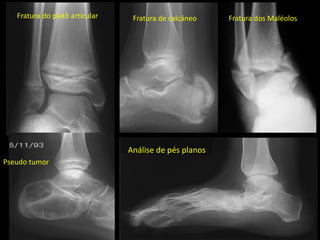

Análise de pés planos

Fratura do platô articular Fratura de calcâneo

Pseudo tumor

Fratura dos Maléolos

PÉ